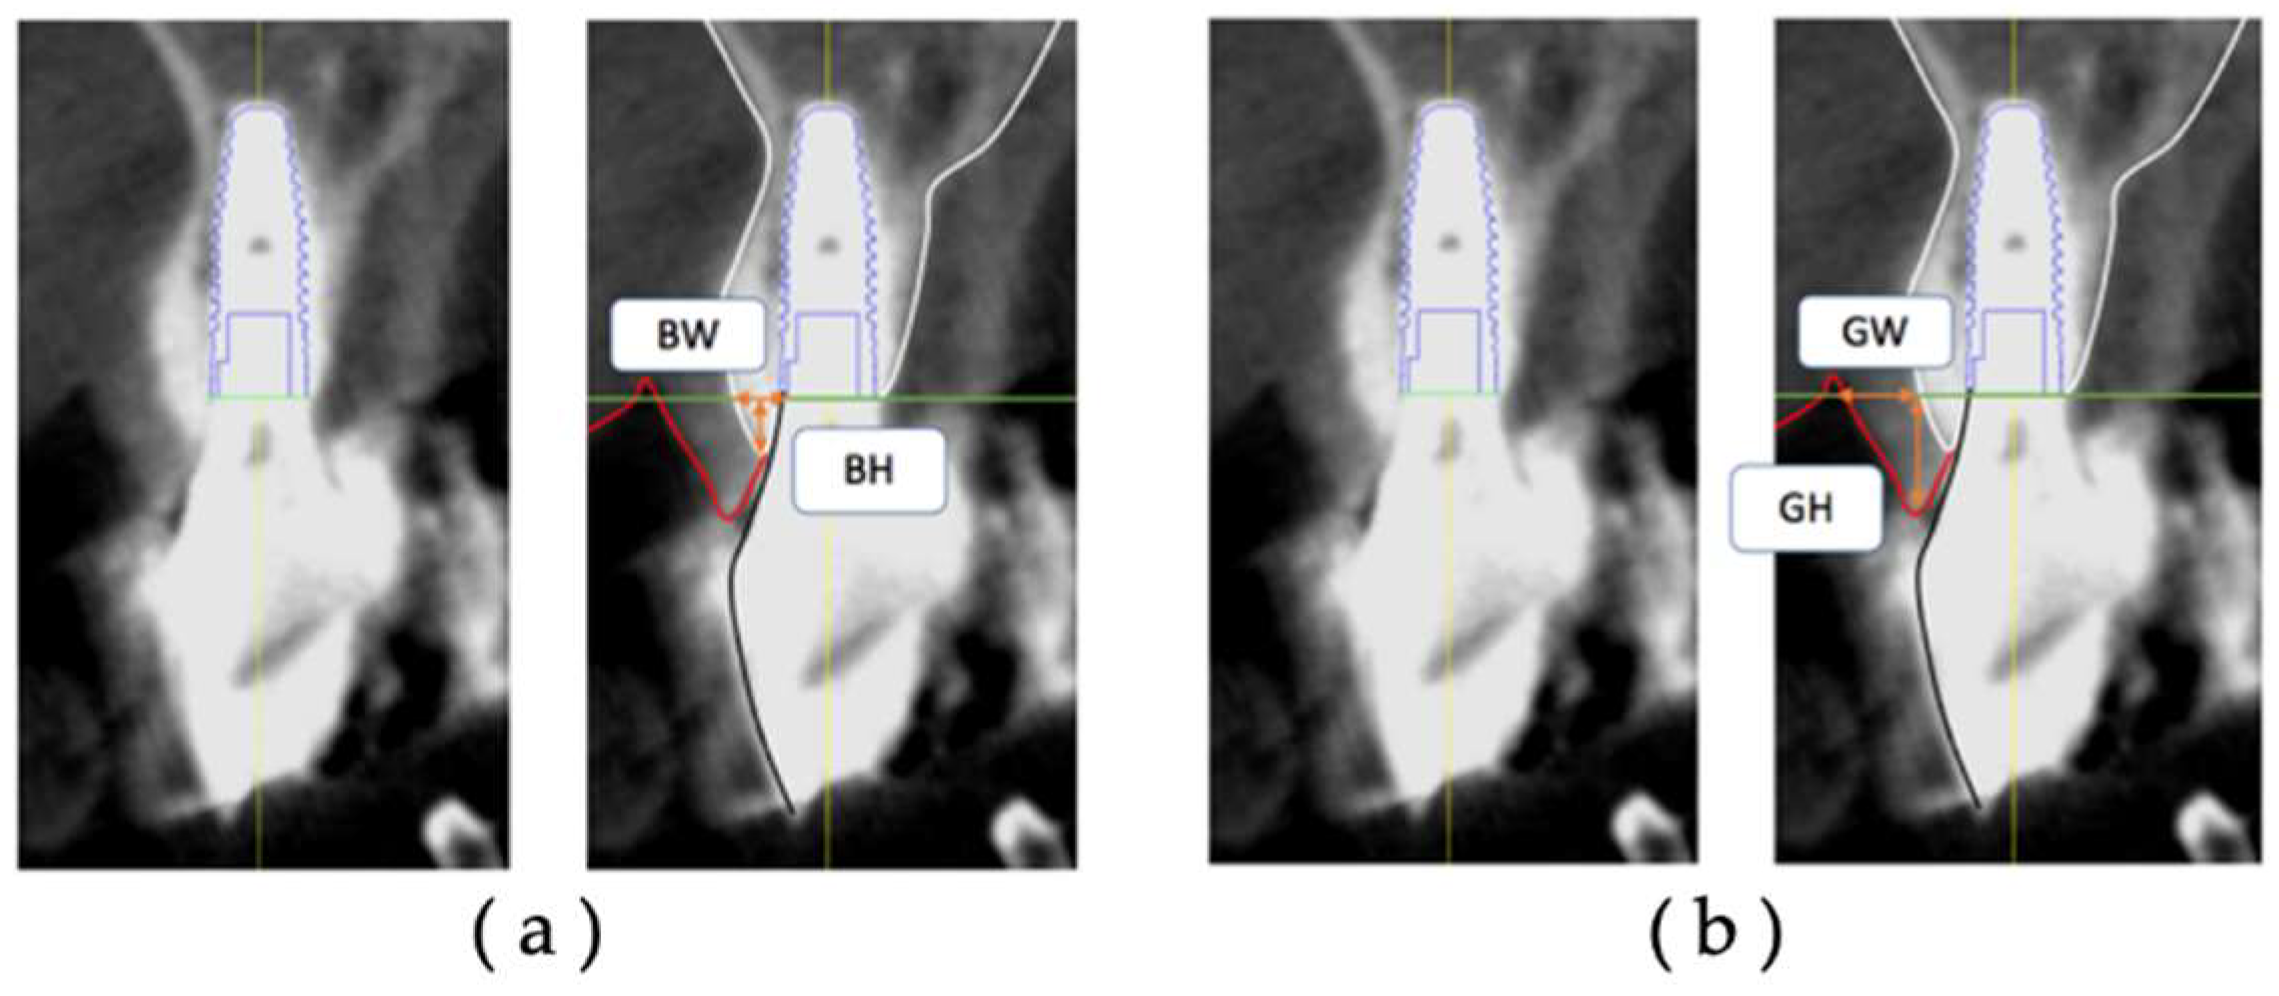

In each group, CBCT data at T1 and T2 were extracted, and postoperative facial tissue of the implant body was measured on diagnostic imaging software.

The thickness (BW) and height (BH) of the facial hard tissue of the implant and the thickness (GW) and height (GH) of the facial soft tissue of the implant were measured at T1 and T2, respectively, based on the platform level in the cross-sectional section (Figure 4). The hard tissue change (ΔBW, ΔBH) and soft tissue change (ΔGW, ΔGH) were calculated from T1 to T2.

Figure 4. Measurement items for postoperative implant facial tissue. Based on the platform level, (a) BW: thickness of the hard tissue on the facial side (including bone replacement material) (mm); (b) BH: height of the hard tissue on the facial side (including bone replacement material) (mm); GW, thickness of the soft tissue on the facial side (mm); GH, height of the soft tissue on the facial side (mm).